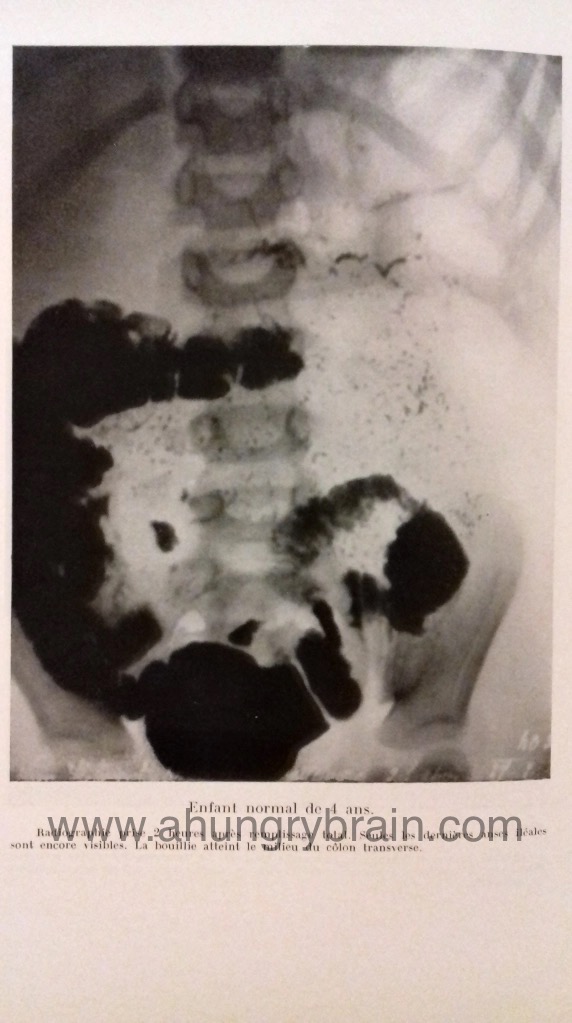

Comme tu peux le constater sur ces quelques photos que j’ai faites de cette thèse datant de 1939, y sont décrites et illustrées, toutes les observations cliniques de cet étrange trouble de la digestion des glucides (on s’en doutait déjà), et le suivi médical de plusieurs petits patients dans un état de dénutrition qui fend littéralement le cœur, tout au long des mois qu’ont duré ces travaux de thèse. En lisant ces travaux, on se rend tout de suite compte de la chance inouïe d’être cœliaque dépistée en 2020 ! Je Me permets donc ici une pensée très émue pour tous ces petits bouts et tous les enfants cœliaques partis trop tôt, parce qu’on ne comprenait pas grand chose à cette pathologie jusqu’à il y a finalement très peu de temps à l’échelle de l’Histoire de l’humanité !